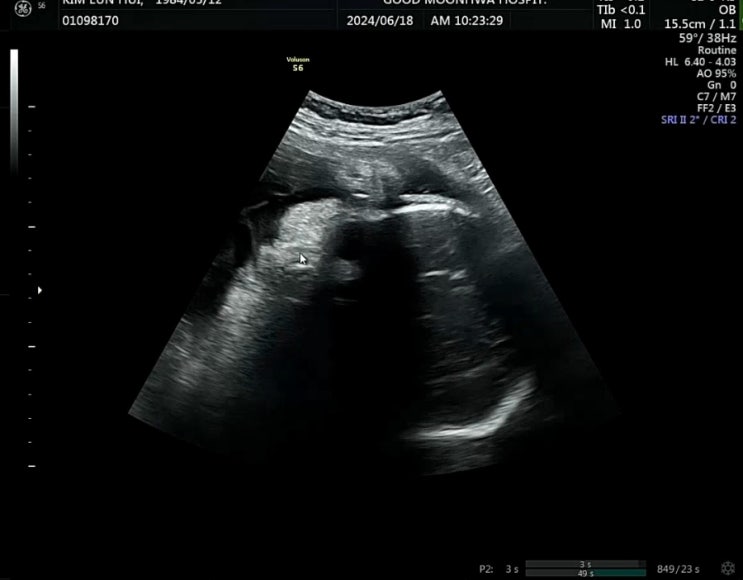

37주 6일

드디어 방빼는 날 잡았어요. 7월 4일 유도 분만 하기로 했어요. 태동 검사 하고 진료실 가서 내진검사 하니...